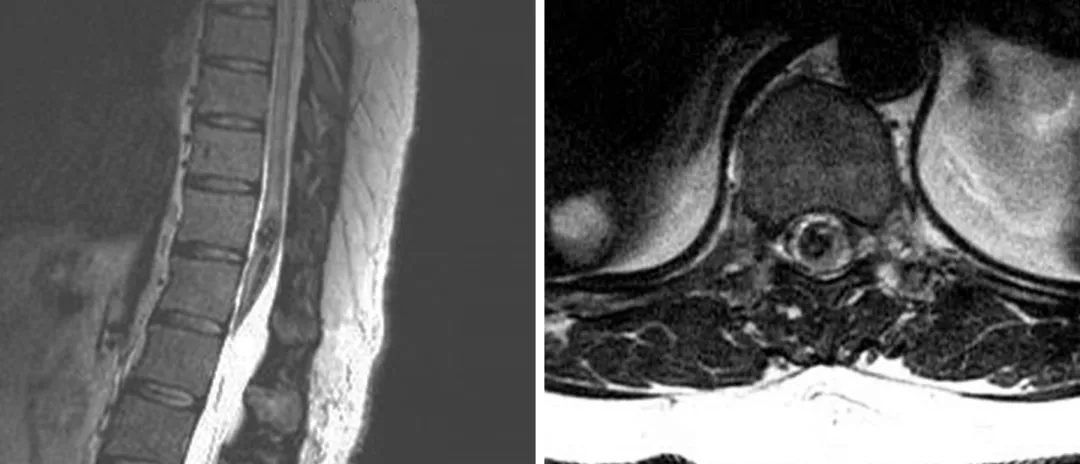

图1:图示一个脊髓圆锥CM。该病灶引起双下肢轻瘫,最终切除。